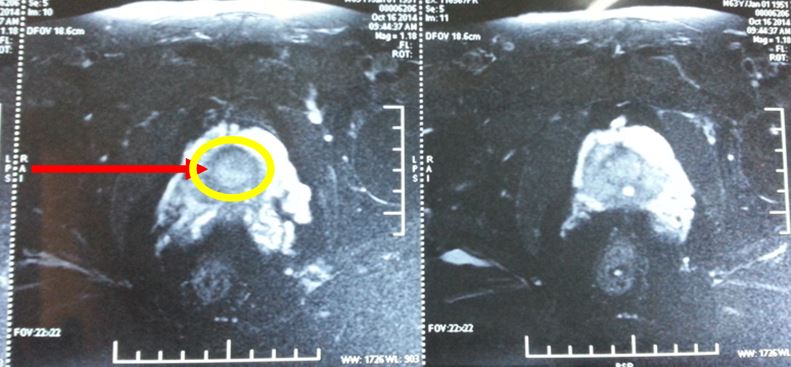

Trên hình ảnh MRI, khối u tuyến tiền liệt ranh giới rõ, bắt thuốc mạnh, kích thước 15 mm, chưa xâm lấn vỏ bao và túi tinh 2 bên.

Trước điều trị: khối u tuyến tiền liệt ranh giới rõ, bắt thuốc mạnh, kích thước 15 mm, chưa xâm lấn vỏ bao và túi tinh 2 bên; PSA = 28,5 ng/ml

Sau điều trị 7 tháng: không còn u trên cộng hưởng từ, nồng độ PSA về bình thường, bệnh nhân hết đi tiểu khó, thể trạng tốt; PSA giảm xuống rất nhiều còn 0,91 ng/ml.